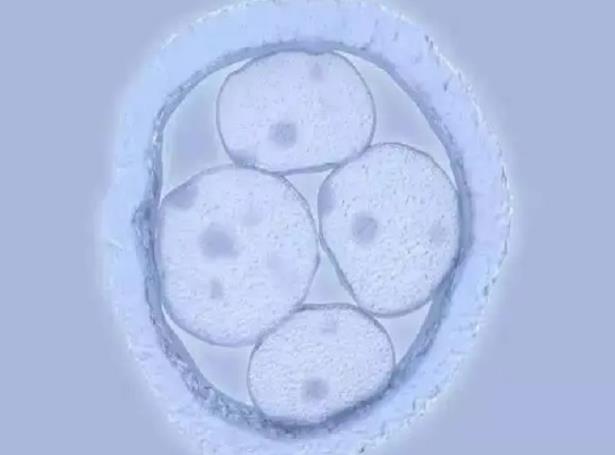

太原供卵助孕代怀生子机构排名,附供卵成功率及费用一览?供(借)卵试管婴儿是将第三者年轻健康的卵子和男方的精子在体外受精,培养成胚胎,然后植入患者宫腔内继续妊娠的过..